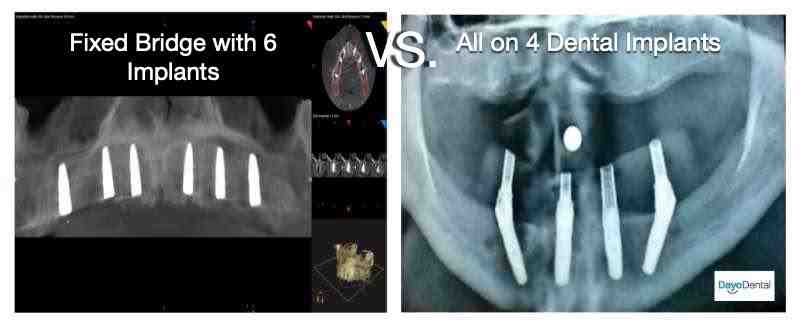

What type of X rays are needed for implant placement?

Cone ray CT is a type of radiography that produces 3D images of dental structures, soft tissues, nerves, and bones. It helps locate dental implants and assesses cysts and tumors in the mouth and face. He may also see problems with gums, tooth roots and jaws.